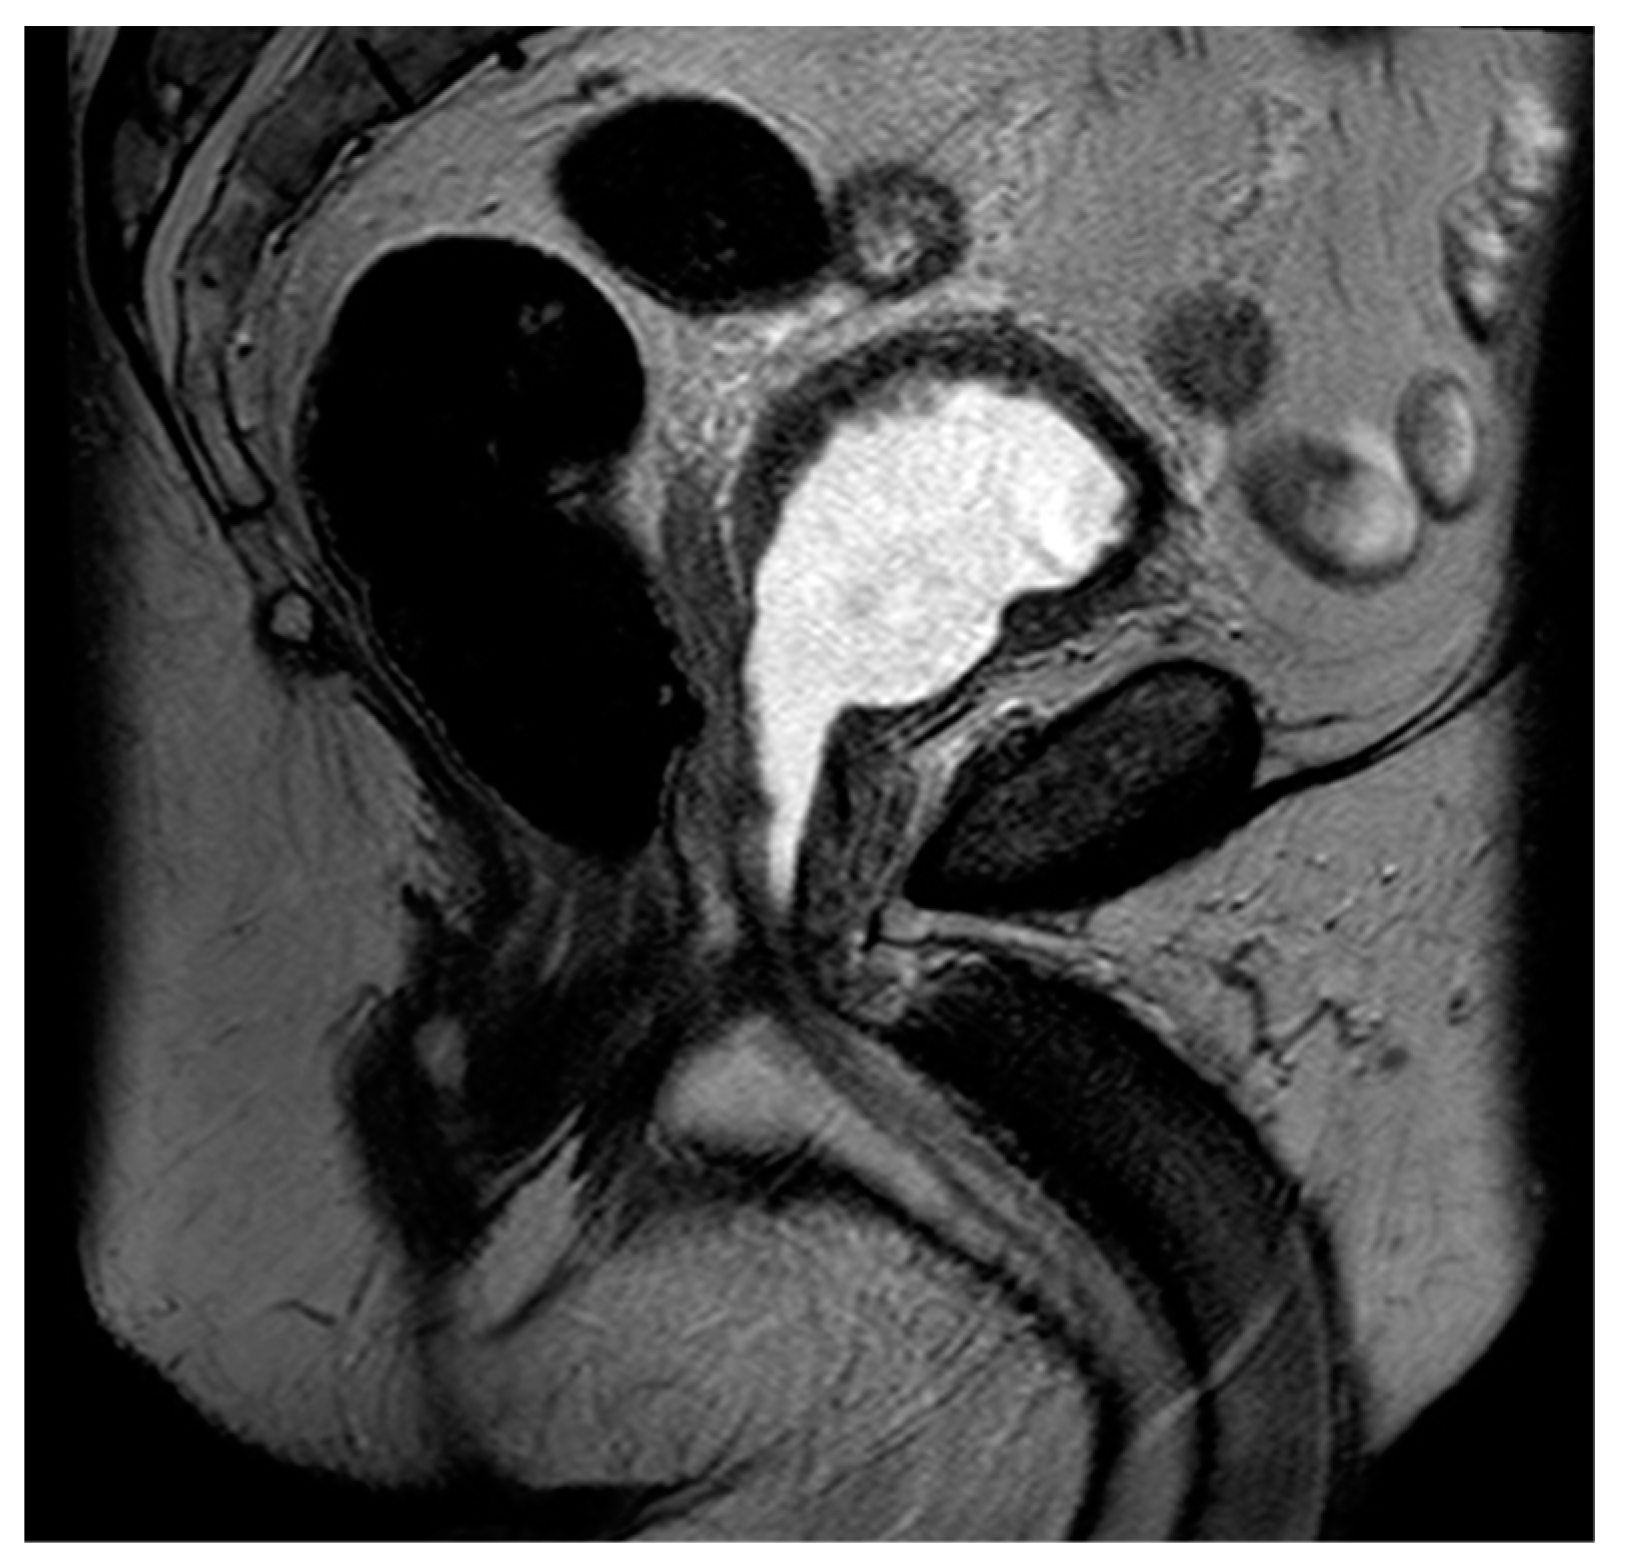

Figure 6. Sagittal T2 image demonstrating post-HoLEP changes to the prostate. As compared to TURP, HoLEP features a wider central defect with less residual peripheral tissue.

Laser enucleation of the prostate (LEP), commonly performed with either a holmium laser (HoLEP) or a thulium laser (ThuLEP), is an ever-increasingly used option for the treatment of BPH. These lasers were first used to vaporize tissue but are now more commonly used to enucleate the entirety of the gland, which is then mechanically morcellated within the bladder in order to facilitate expulsion. One major advantage of LEP, when compared to TURP, is that it is size-independent and can be implemented as a surgical option for glands of varying sizes [71]. When using MRI, LEP procedures look very similar to TURP but often have less residual peripheral tissue and a wider central periurethral defect (Figure 6). There can also be increased T2 intermediate signal and heterogeneity, which can impair the detection of prostate cancers.